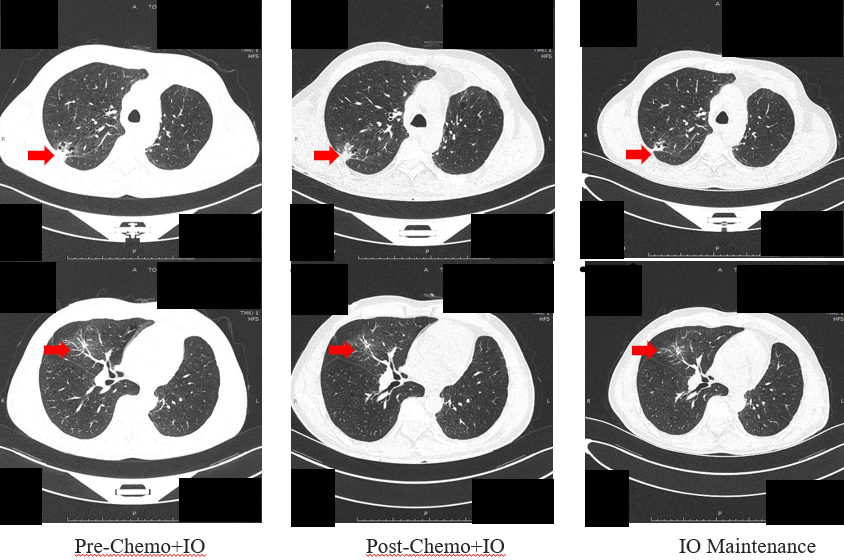

疾病进展:2023年4月复查示右肺结节再次增大。行肺活检及基因检测,未检出敏感基因突变,PD-L1表达15%。

化疗联合免疫治疗:2023年4月至6月,予紫杉醇+铂类方案联合免疫治疗4周期,后于2023-07至2024-06月行免疫治疗单药维持。

第四阶段:寡进展局部干预(2024-06月–至今)

寡进展:2024-06复查示右肺结节进展(寡进展)。

经MDT讨论,决定行手术治疗。